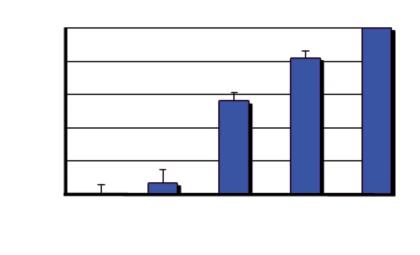

Aumento del numero dei decessi dovuti al cancro nei diversi gruppi di età, dal 1970 al 2000

Età dei pazienti 70 - 79 anni

Età dei pazienti 60 - 69 anni

Età dei pazienti 50 - 59 anni

Dati statistici per gli USA, dati comparabili per l’Europa. Fonte: Journal of the American Medical Association, 2005